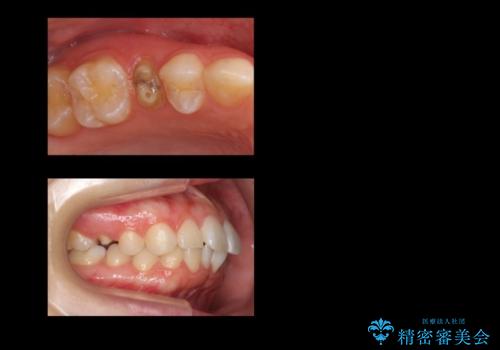

- 他院で治療途中、歯を被せたら頻繁に外れてしまうとのことでした。

診察すると、歯の高さがなく物理的に外れやすい状態となっていました。

歯周外科治療で歯の高さを出し、外れにくくしました。

また、骨の高さを変えずに歯肉の奥深くまで削ると、歯肉の炎症になってしまいます。慢性的な炎症となり、すぐ出血するような状態が治らなくなってしまいます。

そうなると正確な歯型が取れなくなり、被せ物と歯の間に隙間が生じ、虫歯のリスクが飛躍的に高まります。歯肉の奥深くに隙間があるような状態は歯ブラシができないので悪化の一途をたどってしまいます。